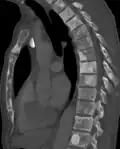

Osteosclerosis can be detected with a simple radiography. There are white portions of the bone which appear due to the increased number of bone trabeculae.